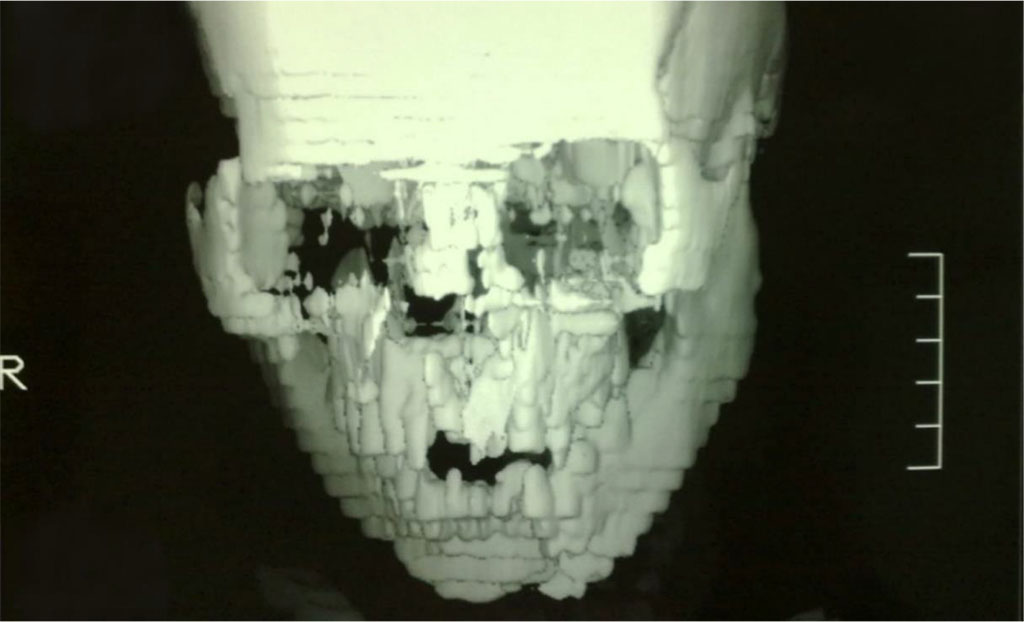

Cranio-facial Multidetector Computerized Tomography (MDCT) confirmed our diagnosis, excluded other fractures, intracranial lesions, cerebral oedema and hemorrhage [Figure 2,3]. The patient was given one gm I.V. CefotaximeTM. The decision was made for closed reduction (except for the mandibular fracture) under general anathesia with nasal intubation.

Figure 2: MDCT showing the maxillary Le Fort I and the left parasymphysial mandibular fractures.

Figure 3: MDCT showing the maxillary Le Fort I and the left parasymphysial mandibular fractures.